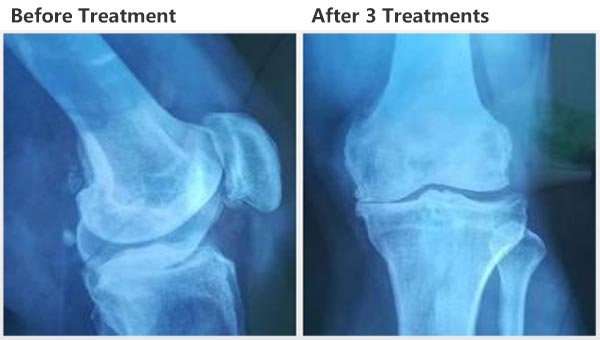

التأثير السريري